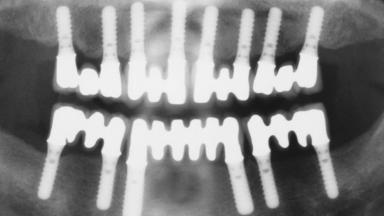

Immediate Loading of Eight Implants in the Maxilla and Six Implants in the Mandible and Final Restoration with Three-Unit and Four-Unit FDPs

# of Implants 14

Type of Implants One-Piece

Defining Characteristics Fully edentulous upper jaw to be rehabilitated with four or more implants

Modality 6+ implants with immediate loading

SAC Level Complex

Defining Characteristics Fully edentulous upper jaw to be rehabilitated with an implant-borne fixed dental prosthesis

Loading Protocol Immediate